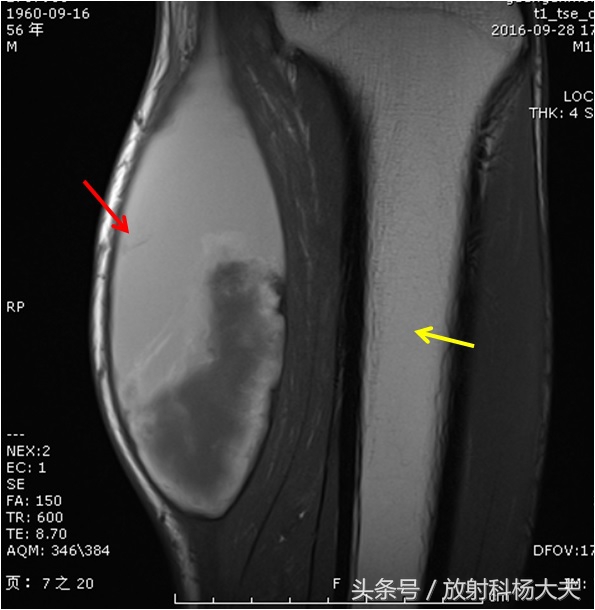

核磁出来了,左腿腓肠肌血肿。

图中红箭所示的白白的区域为血肿,黄箭为小腿的骨骼-胫骨。